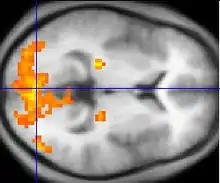

Розрізняють електронний парамагнітний резонанс (ЕПР) та ядерний магнітний резонанс (ЯМР). У першому випадку переходи відбуваються між розщепленими магнітним полем електронними рівнями (дивіться ефект Зеемана). У другому випадку використовуються магнітні спіни нуклонів атомного ядра.